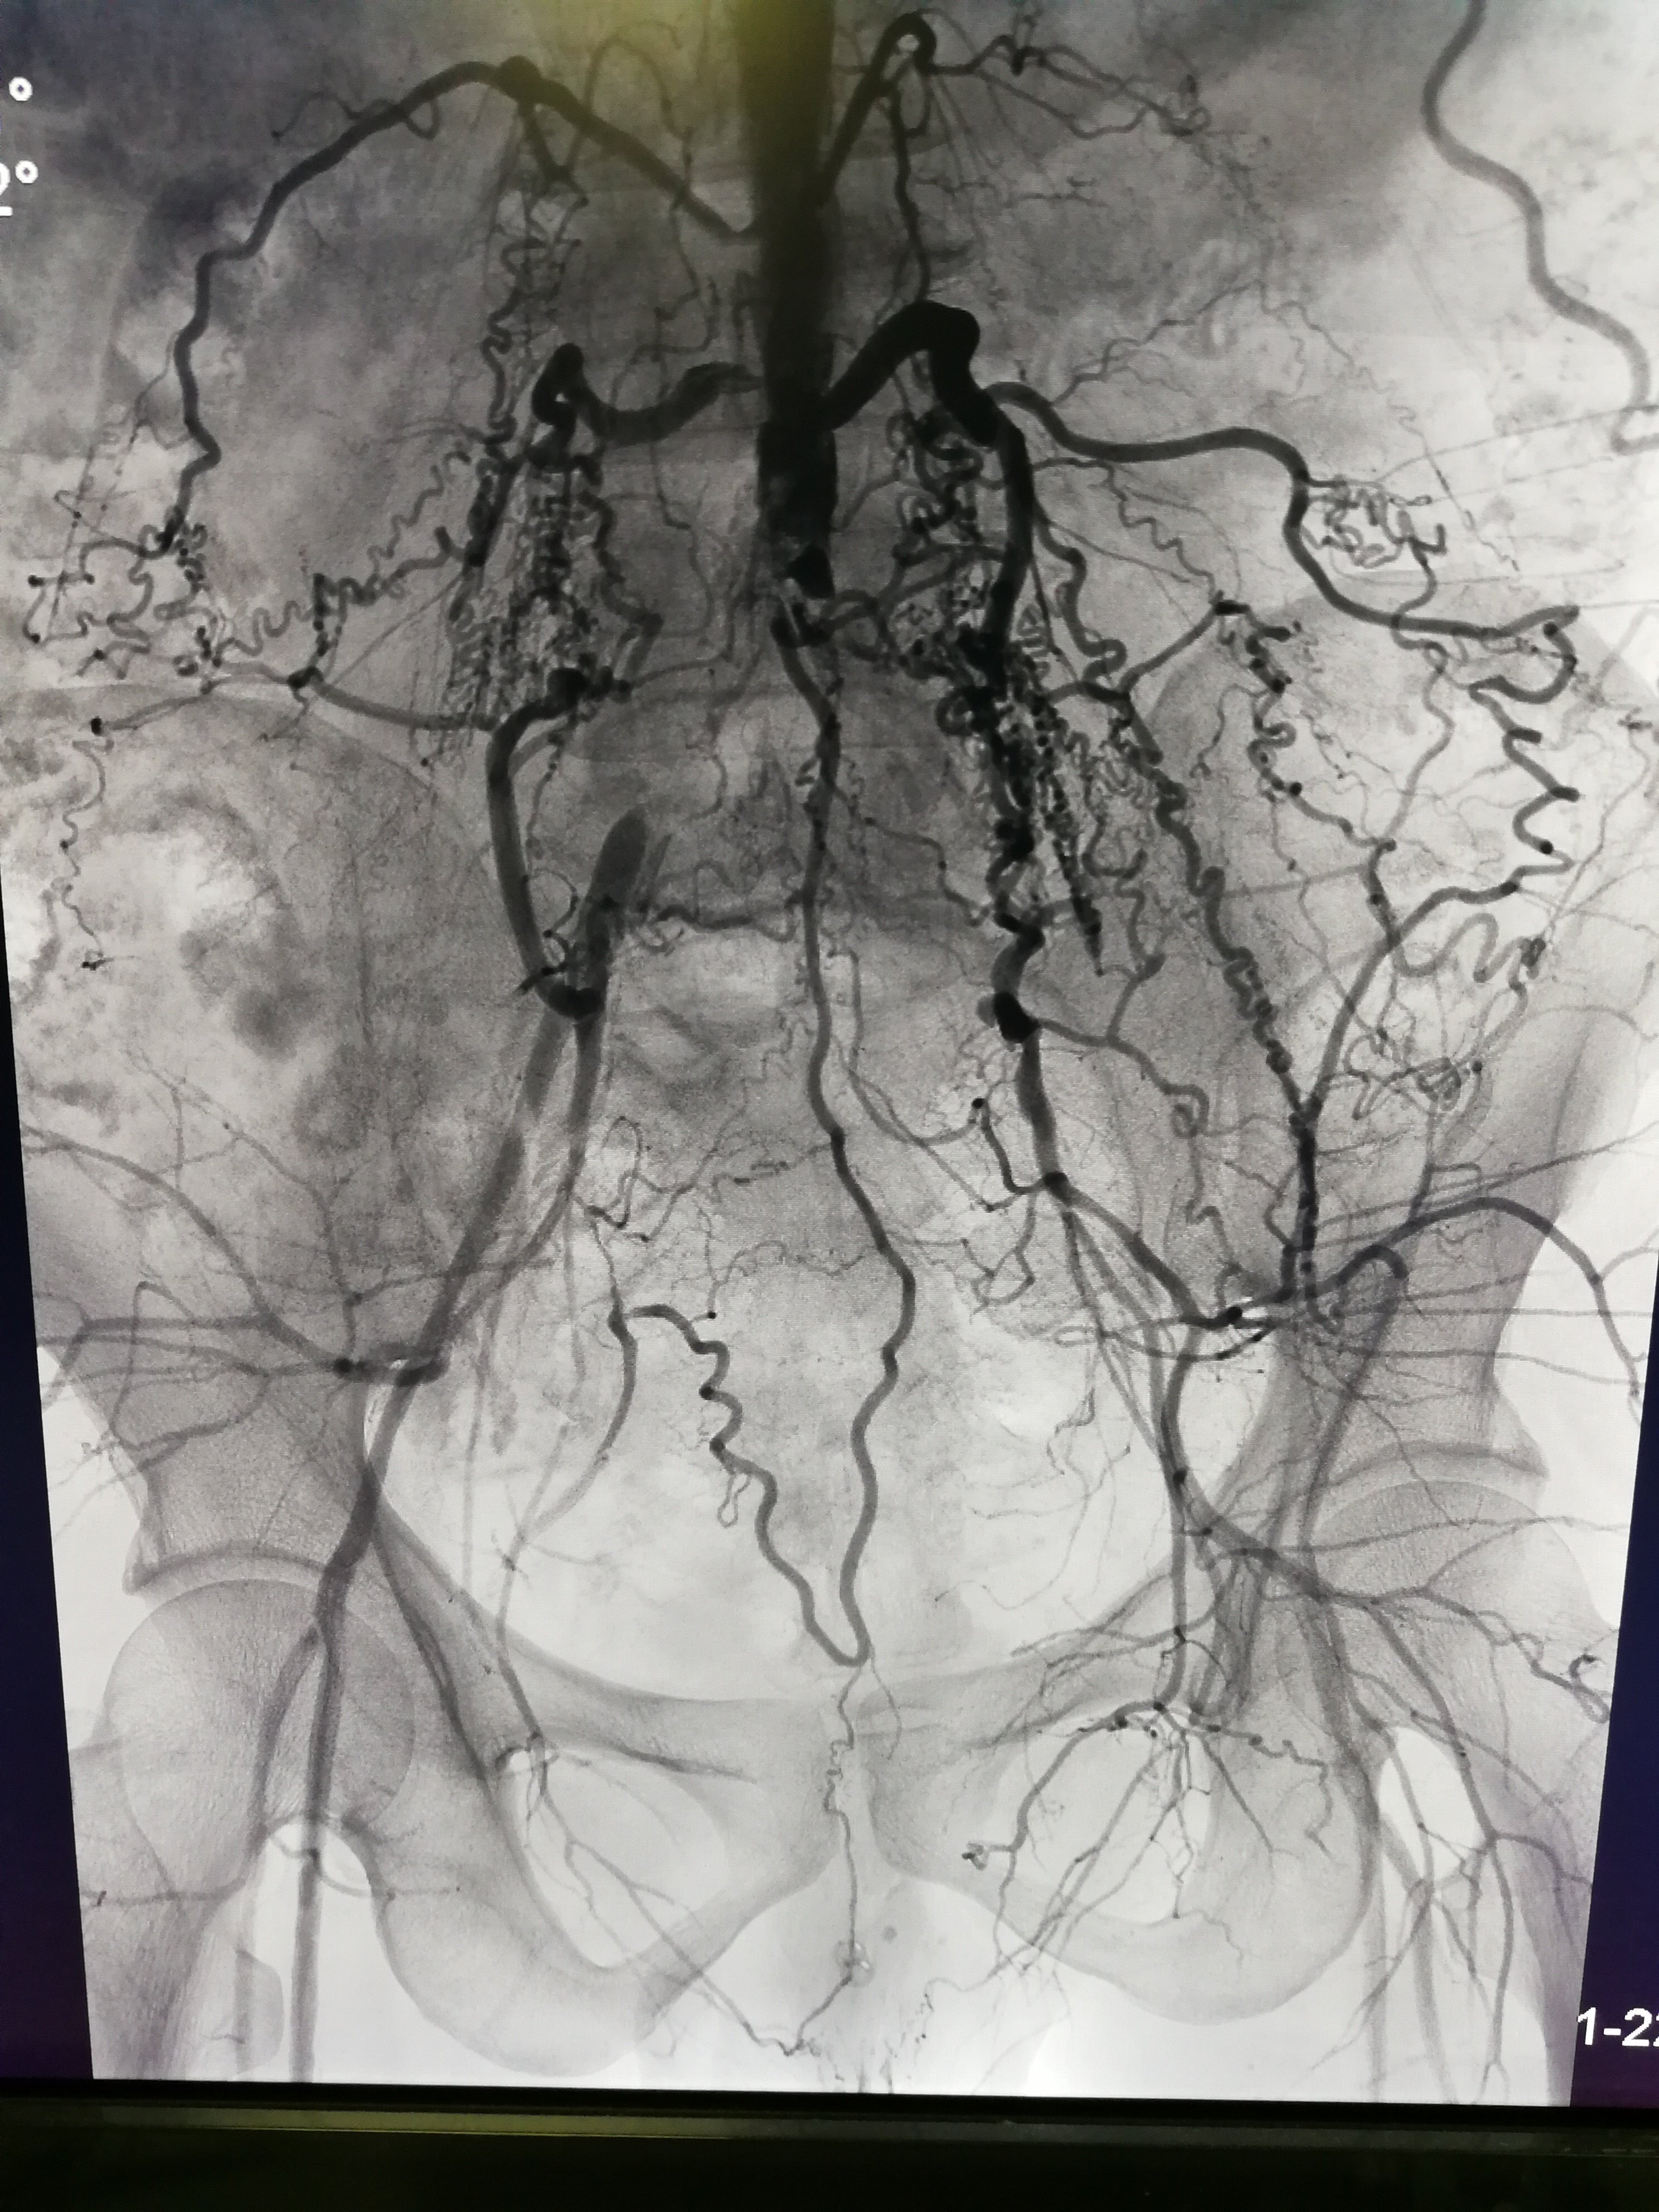

主髂动脉闭塞症微创治疗

图片尺寸2976x3968